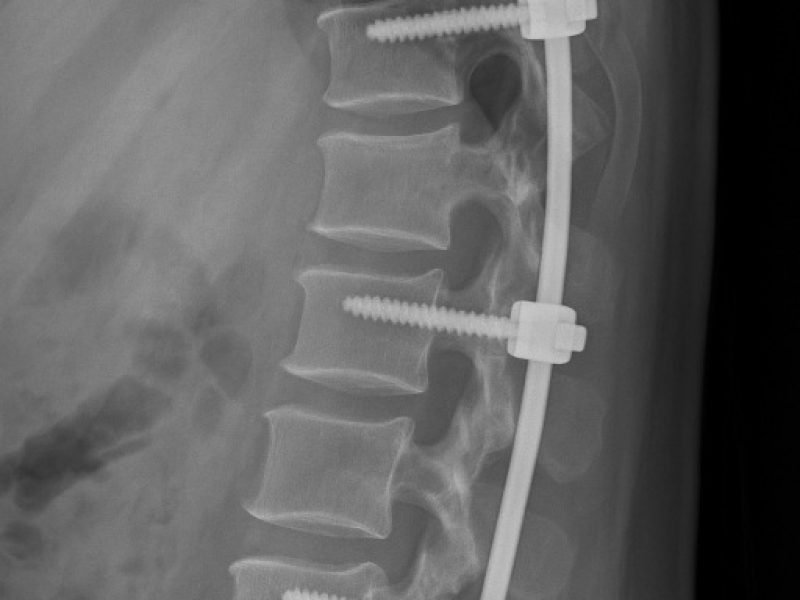

We provide advanced spine surgery to treat a wide range of spinal conditions, focusing on restoring stability, relieving pain, and improving mobility with the least possible disruption.